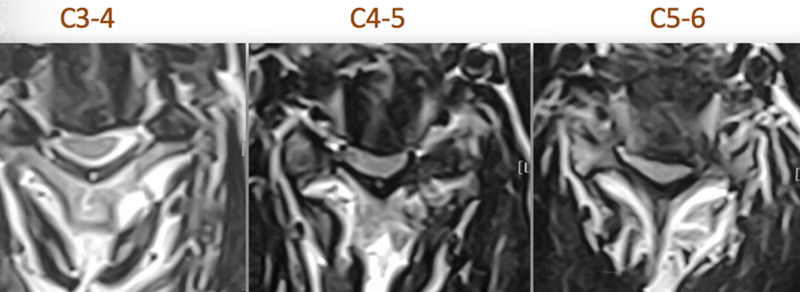

MRI:C3-4后方可见脊髓高信号改变

CT:C5-6